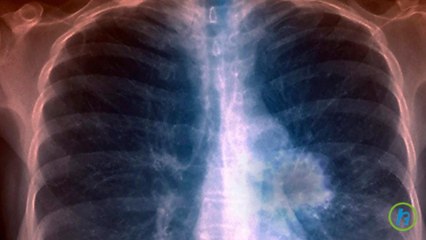

Non-smokers are at risk of lung cancer too.

Smoking is a main risk factor for lung cancer, but what about lung cancer among non-smokers? Consultant Respiratory Medicine and Physician Dr Jamalul Azizi Rahaman explains how non-smokers can get lung cancer too. Watch the full podcast on www.sinardaily.my, YouTube or Facebook.